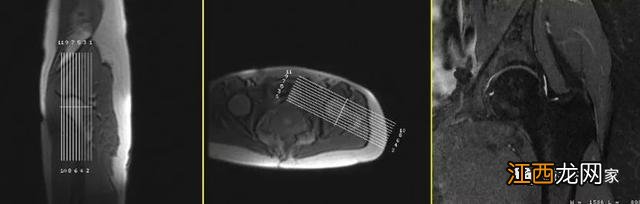

在标准横轴面图像上(如果定位像不好定位,可以先扫描一个标准的横轴面图像再定)定位线平行于股骨颈可以得到斜冠状面图像,髋骨图片构造图解 。

相位编码方向为左右方向 。

采用过采集技术,右侧髋骨图片,防止卷折伪影 。

采用较短TE值,短回波链的高分辨率扫描更有利于显示髋骨关节软骨、盂唇结构 。

斜简冠状面图像主要观察外上盂唇,即11点到3点方向男性 。